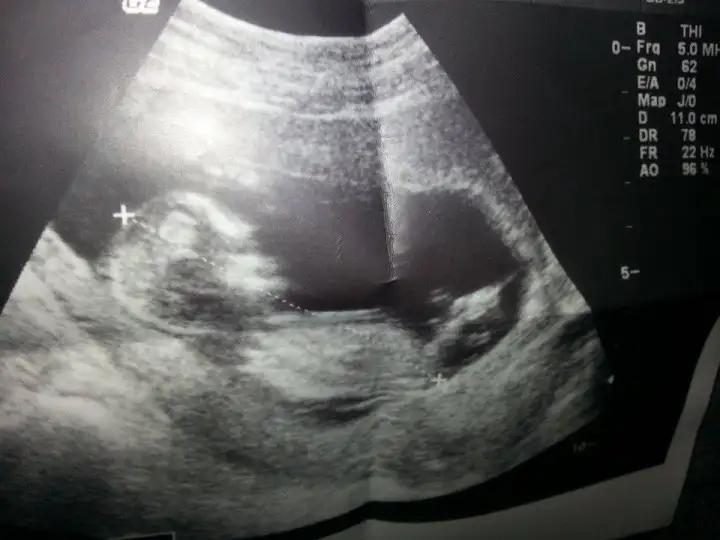

dr soylemeden siz gorun genital nub teorisi ( bebegin cinsiyeti)

bizim bebişin cinsiyeti hakkında fikir alablrmıyım arkadaşlar lütfen yorum bekliyorum özellikle orkide arkadaşım 11+3 bu arada

Zeynep hoca nerelerdeki yorumlarını alsak ben 11*3 demişim bu fotomuz 12*3 haftalık arkadaşlar sizce ne bizim ufaklık